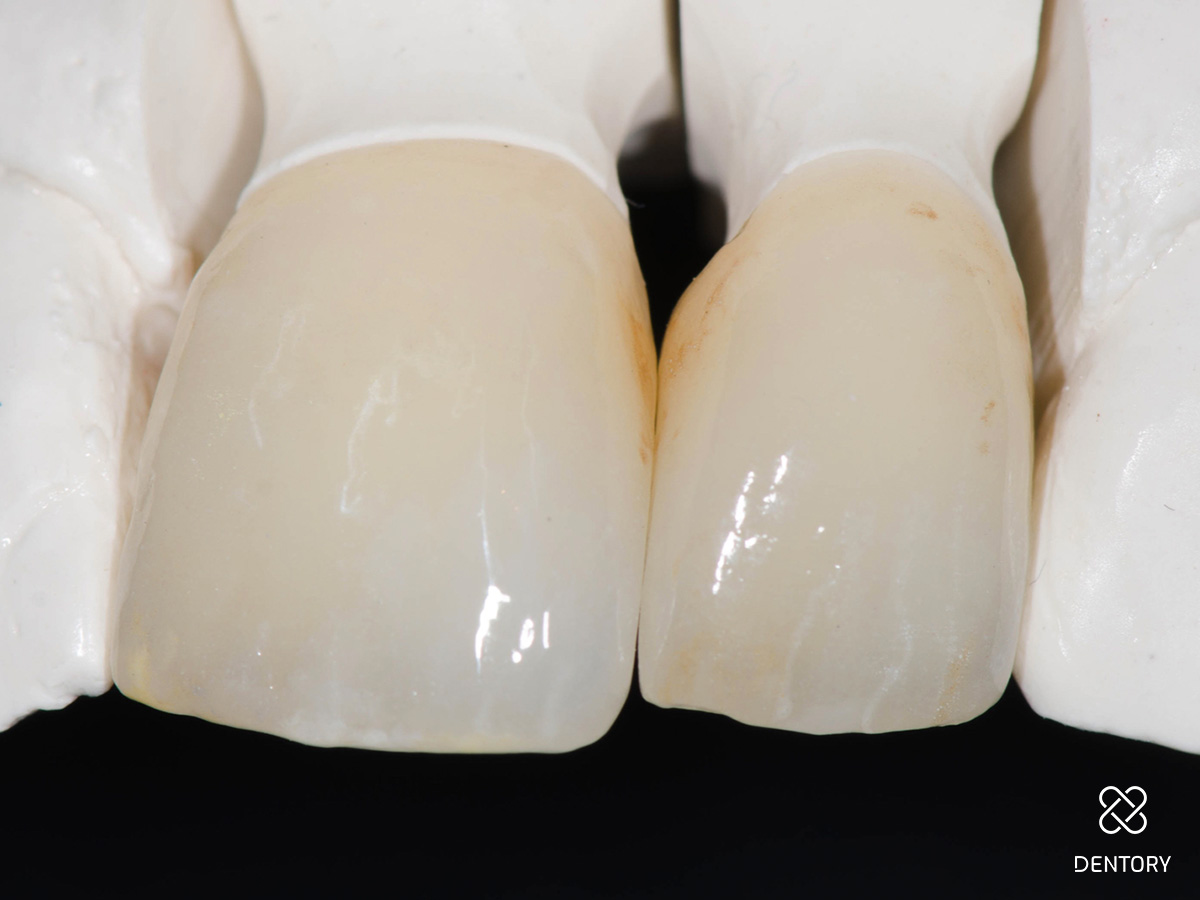

Abbildung 4

Im Labor hergestellte Einzelkronen 21 und 22.